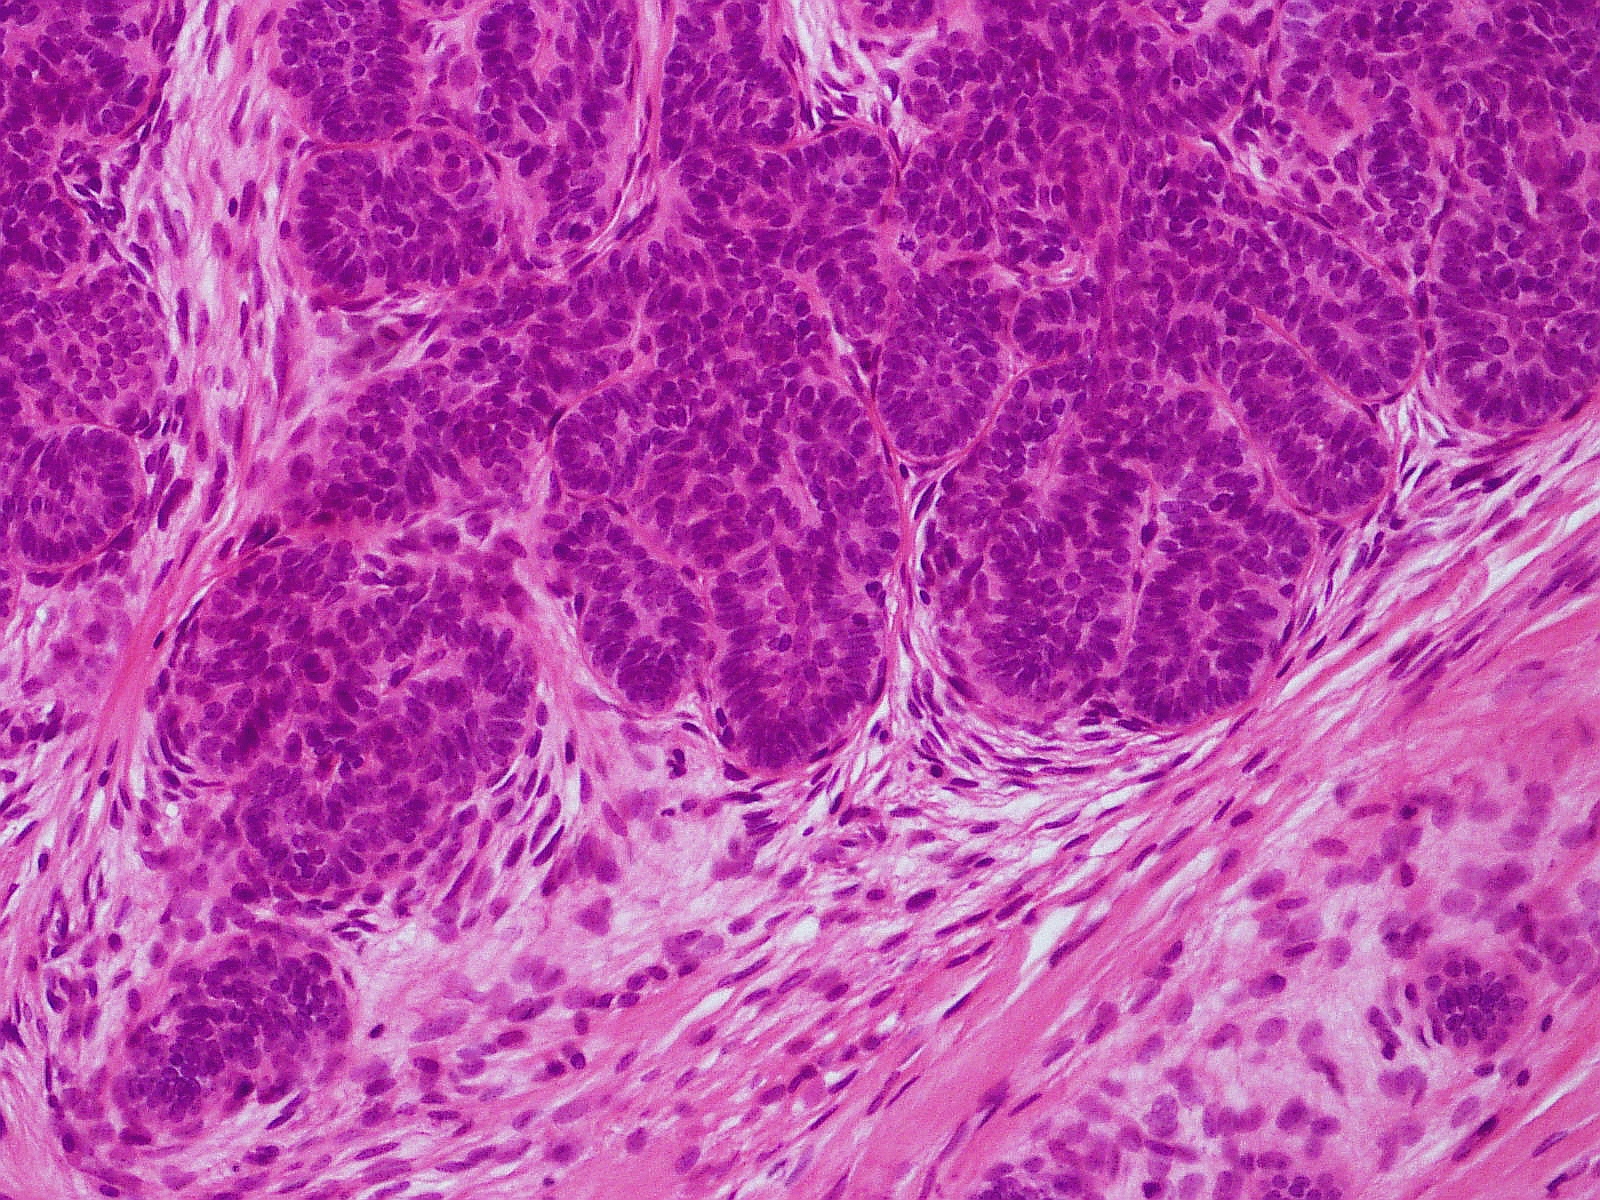

Goed afgrensbaar symmetrisch niet-invasief basaloid tumortje mid-dermaal of laag dermaal, zonder verbinding met de epidermis. Opgebouwd uit regelmatige velden basaloide cellen, die lijken op een basaalcelcarcinoom. Omgeven door een myxoid stroma. In tegenstelling tot een basaalcelcarcinoom geen of zeer weinig mitosen, geen necrose, geen ontstekingsinfiltraat. Immunohistochemie: onderscheid met BCC is te maken met CD10 (cluster of differentiation 10), CD34 (cluster of differentiation 34), CK20 (cytokeratin 20), PHLDA1 (pleckstrin homology-like domain family A member 1 (follicular stem cell)). Trichoblastomen worden door pathologen soms niet herkend en afgegeven als basaalcelcarcinoom.

PA-Foto's: L. Wozniak en K.W. Zielinski - Wikimedia (Creative Commons license 3.0).